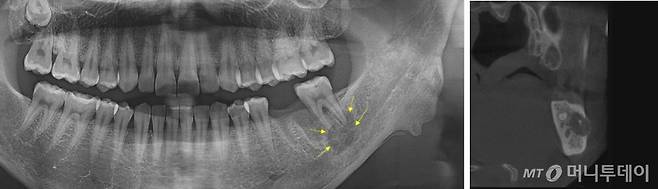

#비교적 치아관리를 잘해온 B씨(50)는 치주질환이 의심돼 지난해 11월 치과에 갔다가 찍힌 영상을 보고 깜짝 놀랐다. 왼쪽 아래턱에 누가 봐도 이상한 게 관찰돼서다. 치과 원장도 종양 같다며 서둘러 대학병원에 가볼 것을 권했다. 하지만 서울대치과병원의 영상판독 결과는 종양이 아니라 ‘하악골 설측 함요’였다. 단순히 뼈가 채워지지 않은 결손 부위였다.

전문의의 원격판독은 환자의 불필요한 시간 낭비와 의료비 경감에도 도움이 된다. B씨처럼 파노라마영상에서는 종양이나 물혹으로 오인될 수 있는 레벨2의 진단도 나오기 때문이다.

허경회 서울대치과병원 영상치의학과 교수는 “사진상 물혹이나 양성종양 등의 특징적인 소견이 보여 동네치과에서 리퍼(refer·협진의뢰)해 내원하는 환자들이 있다”며 “상악동이 크게 보이거나 선천적으로 뼈가 결손된 경우인데 영상치의학 전문가는 이런 경우 치아뿌리를 둘러싼 하얀 치조백선을 같이 보면서 진단한다”고 설명했다.

메디파트너치과 영상센터에 따르면 선천적인 뼈의 결손 부위가 물혹처럼 보이는 ‘스타프네’(Stafne’s cyst)는 0.05%(11건), 뼈의 석회화가 심해 나타나는 골경화증 또는 골형성이상이 0.61%(134건) 등이다. 정 센터장은 “이러한 이상 소견들은 상급병원에 갈 필요가 없다”며 “하지만 일반인이 보기에도 이상하다고 볼 수 있기 때문에 전문적인 영상판독이 중요하다”고 말했다.